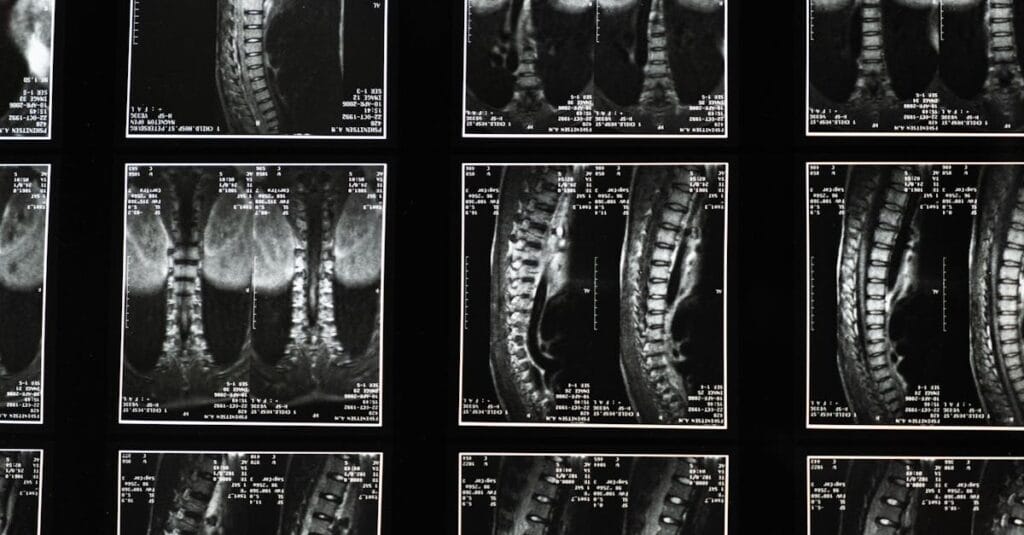

Sténose spinale et décompression neurovertébrale

Ce podcast décrit la sténose spinale, un rétrécissement du canal rachidien comprimant la moelle épinière ou les nerfs. Il détaille ses causes (dégénératives, structurelles, traumatiques, congénitales), symptômes […]